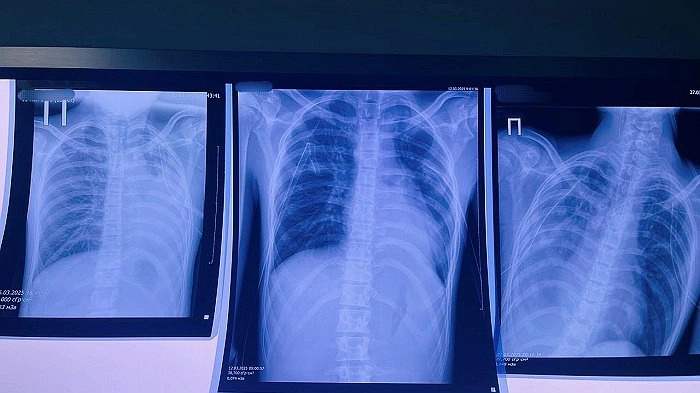

Один из последних инцидентов едва не стоил жизни 16-летнему юноше — у него произошел разрыв булл в легких, вызвавший опасное состояние — двусторонний пневмоторакс. После экстренной операции пациента пришлось перевести в федеральную клинику, где он продолжает борьбу за жизнь.

Медики отмечают тревожную тенденцию: все чаще у молодых вейперов диагностируют EVALI — особую форму поражения легких, связанную с токсичным воздействием веществ из электронных сигарет. Особую опасность представляет ацетат витамина Е, который при нагревании превращается в вязкую массу, намертво прилипающую к легочной ткани.

Хирург Виталий Лапшин предупреждает: образовавшиеся в легких воздушные пузыри могут разорваться в любой момент, что создает прямую угрозу жизни. Медики настаивают — вейпинг не является безопасной альтернативой курению и представляет особую опасность для развивающегося организма подростков.